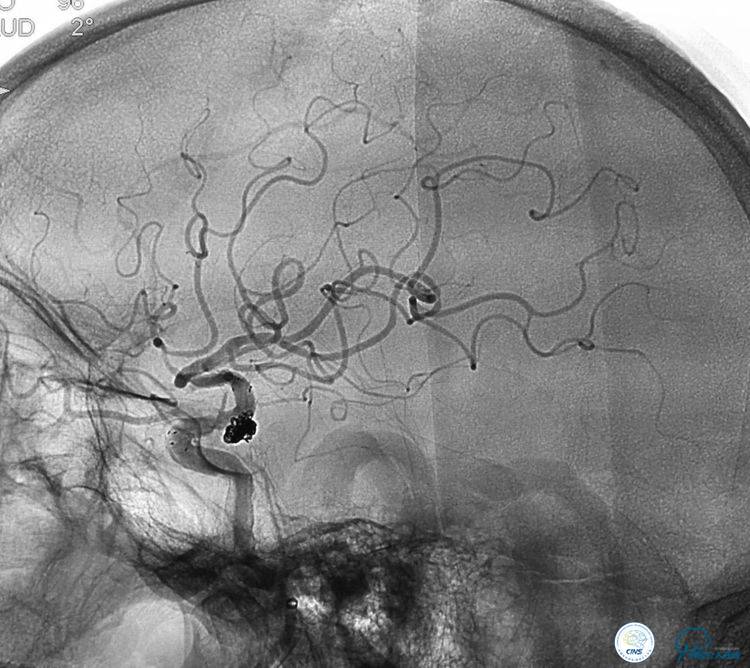

患者,男,72岁,左侧后交通未破裂宽颈不规动脉,同侧交通段有个80一90%狭窄。

1. 路途迂曲,右侧髂动脉迂曲,左颈总动脉迂曲,左颈内动脉开口狭窄50%左右。

2. 载瘤动脉近端严重狭窄。

3. 动脉瘤宽颈,形态不规则呈分叶状。

▼全麻后,导引导管到位以后,选择合适的工作角度。